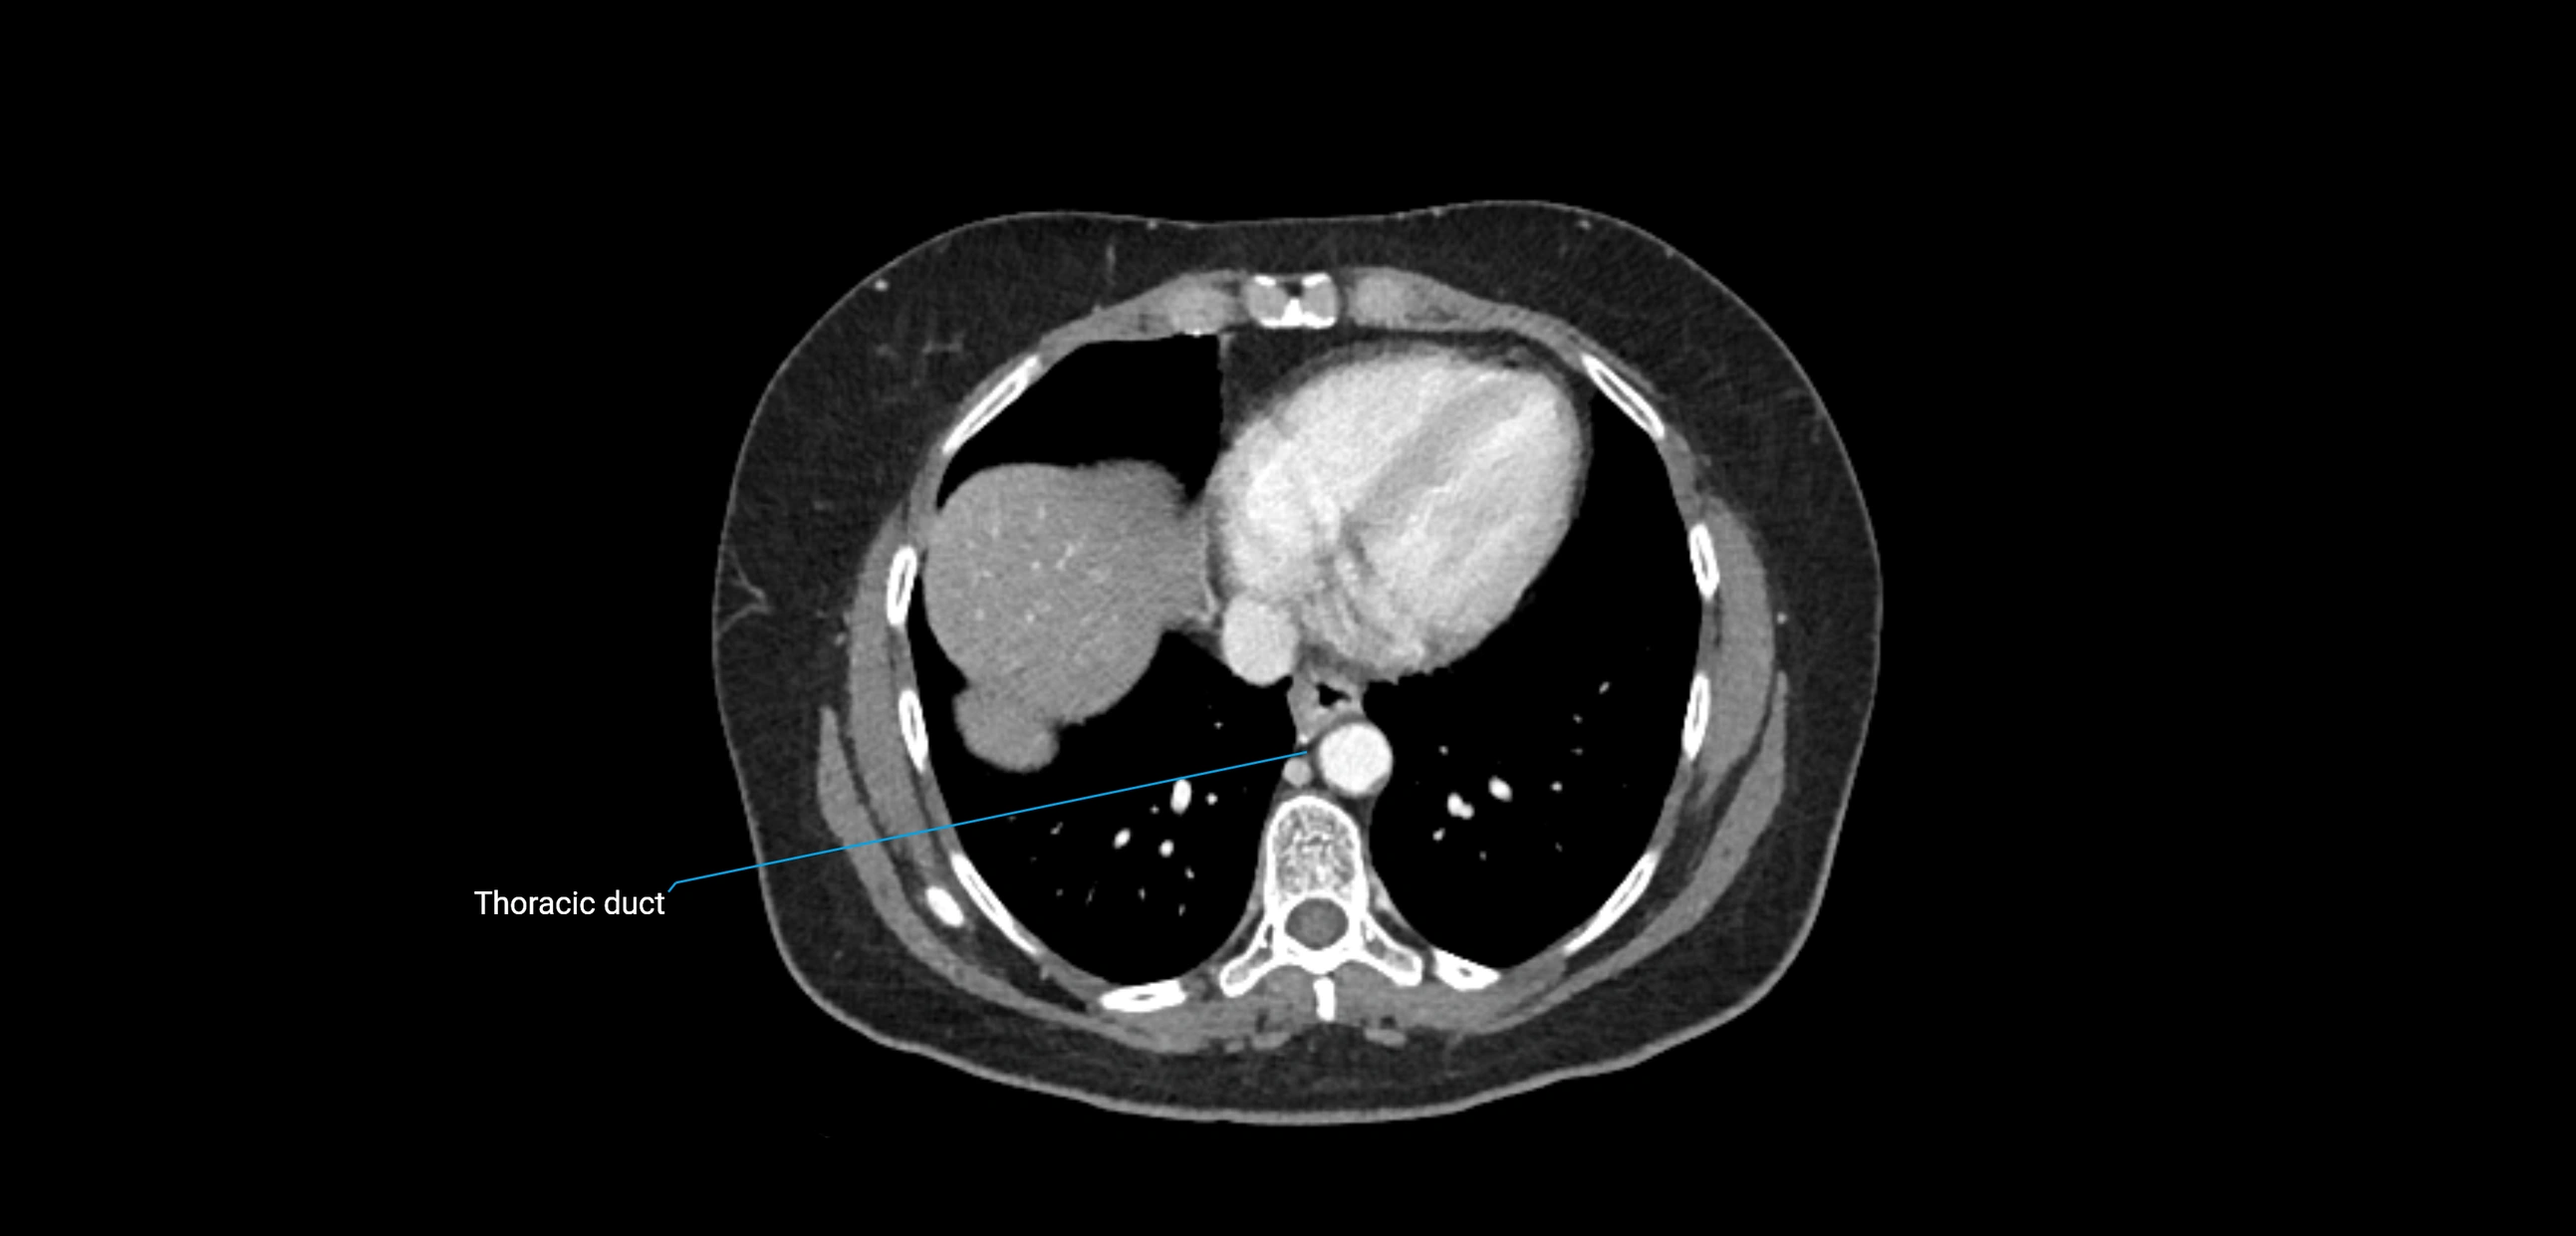

CT Venography (CTV):

• Demonstrates nodal encasement or compression of adjacent vessels (aorta, IVC, renal veins)

• Useful in staging testicular and ovarian malignancies

• Provides 3D reconstructions for retroperitoneal lymph node dissection planning